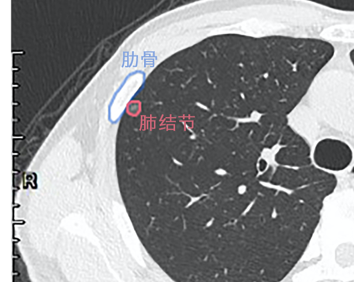

难点 位置刁钻、无法精准定位

解决 定位+手术,避免奔波之苦